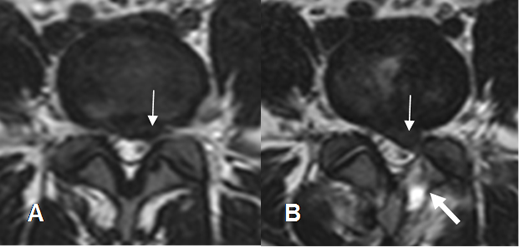

Fig 112. Recidiva de hernia.

A: RM axial en T2. Presencia de hernia paramediana izquierda.

B: RM axial en T2. Laminectomía izquierda, con escasa cantidad de líquido. (Flecha gruesa).

Después de un esfuerzo hay reaparición de los síntomas y formación de una nueva hernia, mas grande que la inicial. (Flecha delgada).